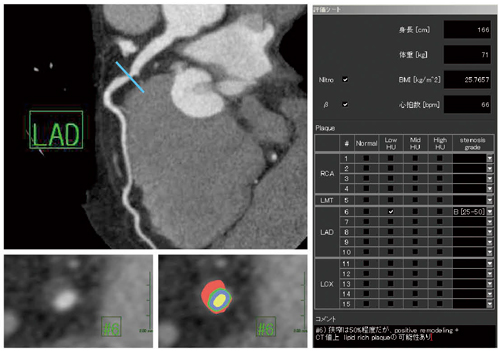

また,AZE VirtualPlace 雷神 Anatomiaは,チェックシート形式の冠動脈レポート作成機能も搭載しており,診療放射線技師にとって,読影医,依頼医との情報の共有,および,医療スタッフとして専門性を生かした画像診断における読影の補助を行うという任務に貢献すると思われる(図6)。

図6 冠動脈レポート画面

チェックシート形式になっており,DICOM画像として保存,CSV出力も可能であることから,情報の共有に有効なツールとなっている。